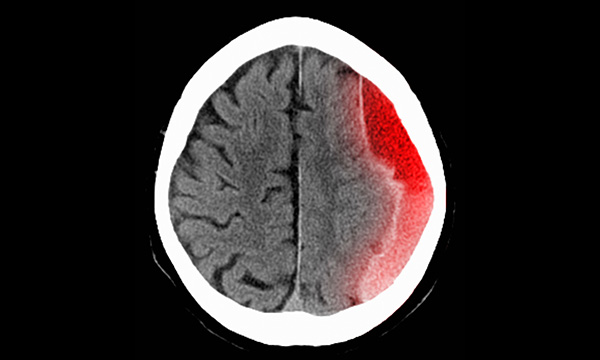

Background Although more men than women sustain a traumatic brain injury (TBI), approximately one quarter of people with TBIs are women. The experiences of TBI reported in the literature are informed from the masculine perspective and do not adequately represent women’s experiences. Pragmatism provides an overarching methodological framework to explore and critique a broader perspective of health, including psychosocial, cultural, spiritual, political and environmental factors, while attempting to address gender inequity.